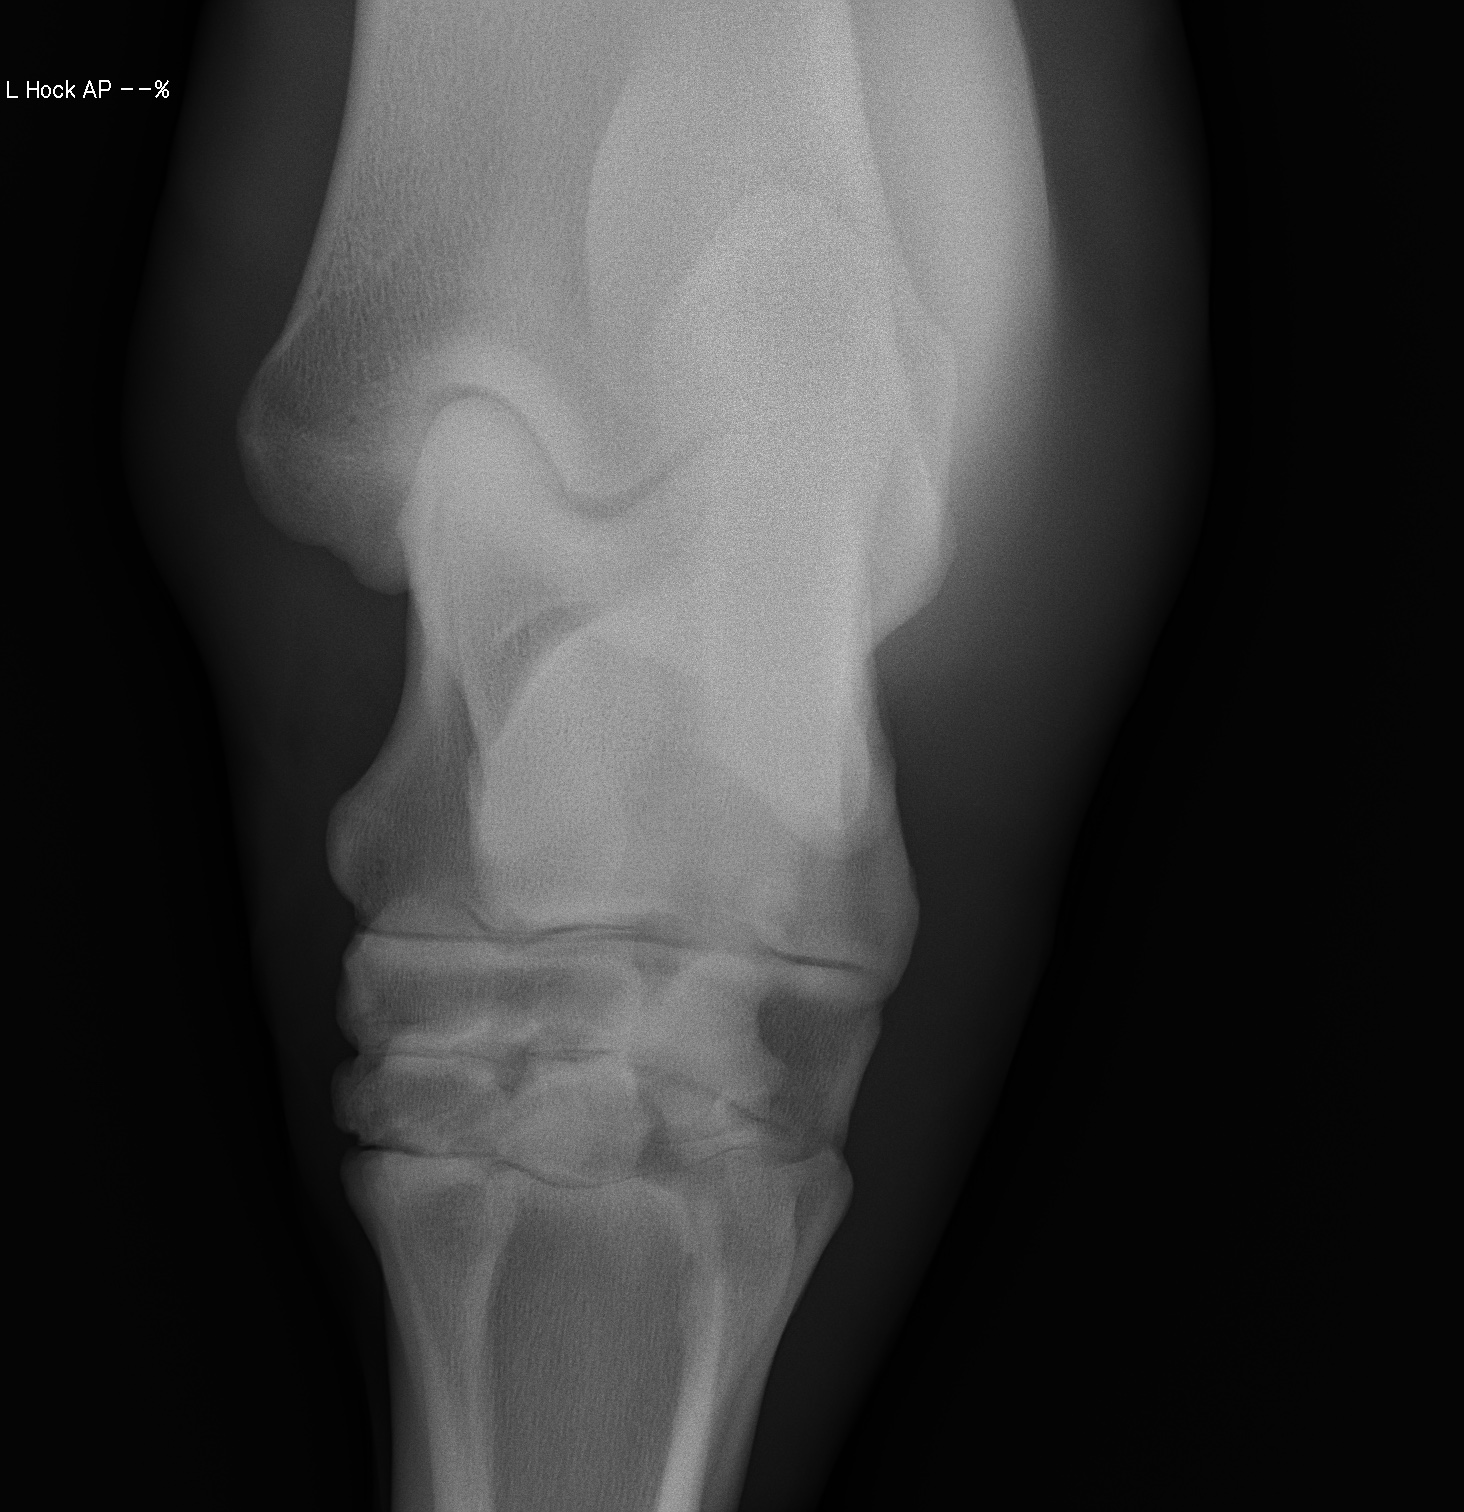

添付のレントゲン画像をご確認ください。現状渡しのノークレームノーリターンでお願いいたします。記載事項に関するキャンセルには応じられません。

※2022年12月17日の競走にて左後脛骨不全骨折を発症しています(全治6~9ヵ月)。